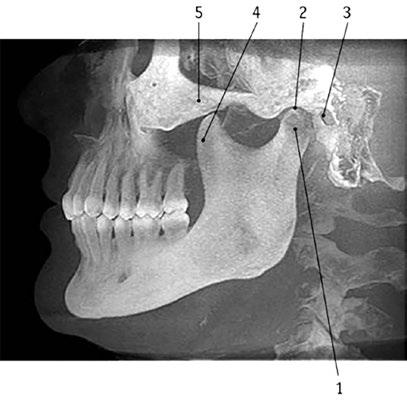

Čelistní (temporomandibulární) kloub TMK – articulatio temporomandibularis („articulus mandibularis“; angl. temporomandibular joint, TMJ) – je jediné kloubní spojení mezi kostmi lebky (obr. 1.1). V lidském těle se

Obr. 1.1 Temporomandibulární kloub z laterálního pohledu. Snímek získán prostřednictvím Cone Beam CT.

1 caput mandibulae

2 jamka čelistního kloubu na os temporale

3 vnější zvukovod

4 processus coronoideus mandibulae

5 arcus zygomaticus

CT – výpočetní tomografie